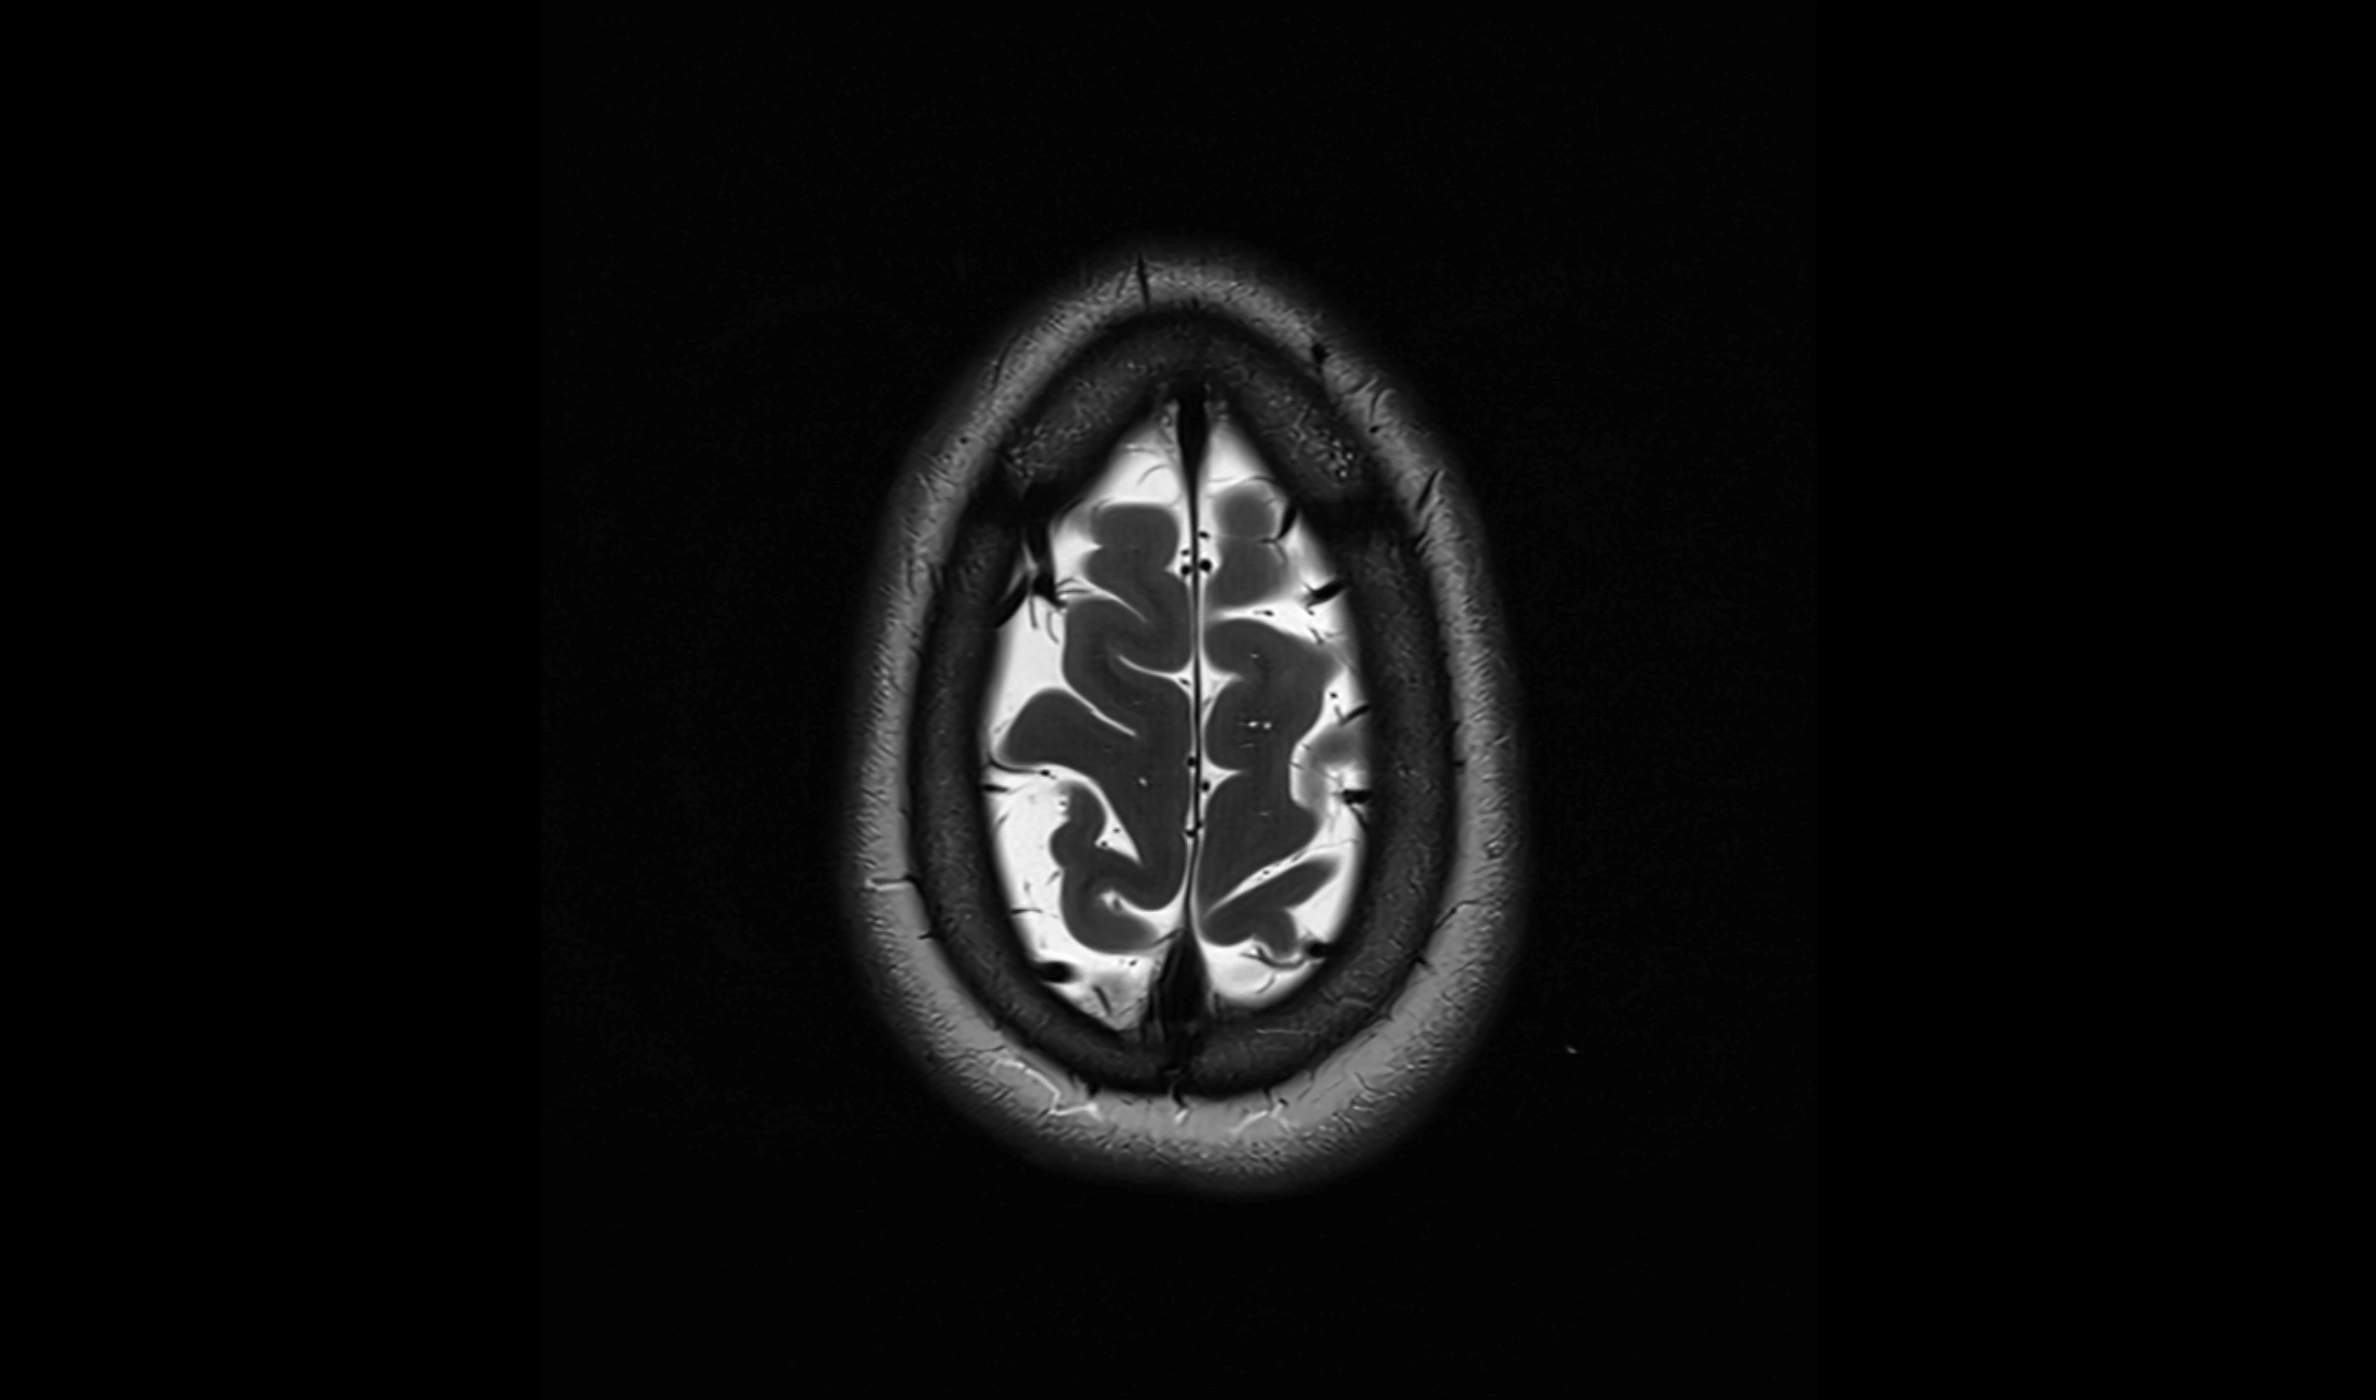

MRI images

image